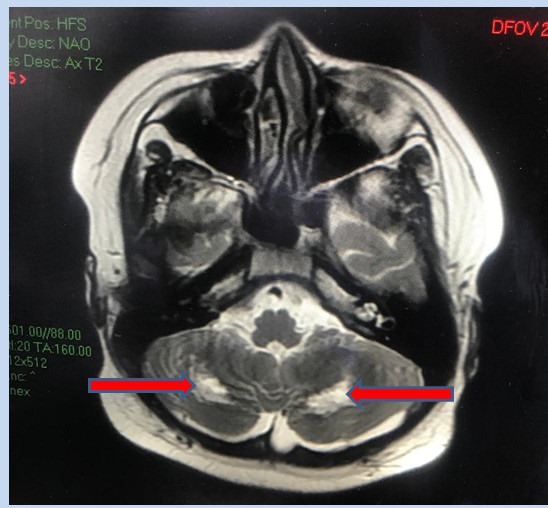

Bệnh nhi tổn thương gan, thần kinh nặng vì mắc COVID-19

TPHCM - Sau 6 ngày mắc COVID-19, bệnh nhi trong tình trạng lừ đừ, thở co kéo. Kết quả MRI não ghi nhận tổn thương đồi thị hai bên, tổn thương chất trắng của tiểu não.